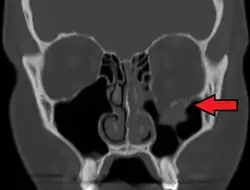

Orbital blowout fracture

| An orbital blowout fracture of the floor of the left orbit. | |

An orbital blowout fracture is a traumatic deformity of the orbital floor or medial wall that typically results from the impact of a blunt object larger than the orbital aperture, or eye socket.[1] Most commonly this results in a herniation of orbital contents through the orbital fractures.[1] The proximity of maxillary and ethmoidal sinus increases the susceptibility of the floor and medial wall for the orbital blowout fracture in these anatomical sites.[2] Most commonly, the inferior orbital wall, or the floor, is likely to collapse, because the bones of the roof and lateral walls are robust.[2] Although the bone forming the medial wall is the thinnest, it is buttressed by the bone separating the ethmoidal air cells.[2] The comparatively thin bone of the floor of the orbit and roof of the maxillary sinus has no support and so the inferior wall collapses mostly. Therefore, medial wall blowout fractures are the second-most common, and superior wall, or roof and lateral wall, blowout fractures are uncommon and rare, respectively. They are characterized by double vision, sunken ocular globes, and loss of sensation of the cheek and upper gums from infraorbital nerve injury.[3]

Thin cut (2-3mm) CT scan with axial and coronal view is the optimal study of choice for orbital fractures.[16][17]